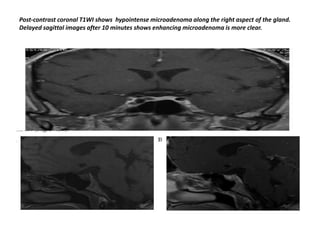

Post-contrast coronal T1WI shows hypointense microadenoma along the right aspect of the gland.

Delayed sagittal images after 10 minutes shows enhancing microadenoma is more clear.